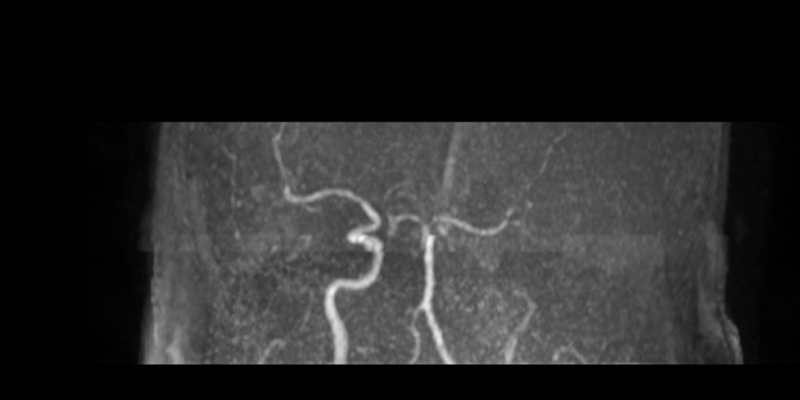

Phim MRI sau 1 ngày can thiệp

Kíp can thiệp do Th.bác sĩ Giáp Hùng Mạnh, Trưởng khoa Thần kinh VLTL-PHCN, Bệnh viện Bãi Cháy cùng ê kíp thực hiện. Sau can thiệp, tình trạng người bệnh ổn định, tỉnh táo hơn, cải thiện vận động, sức cơ chân phải đạt 3/5, huyết áp 110/70 mmHg và đang tiếp tục được theo dõi, điều trị tại bệnh viện.